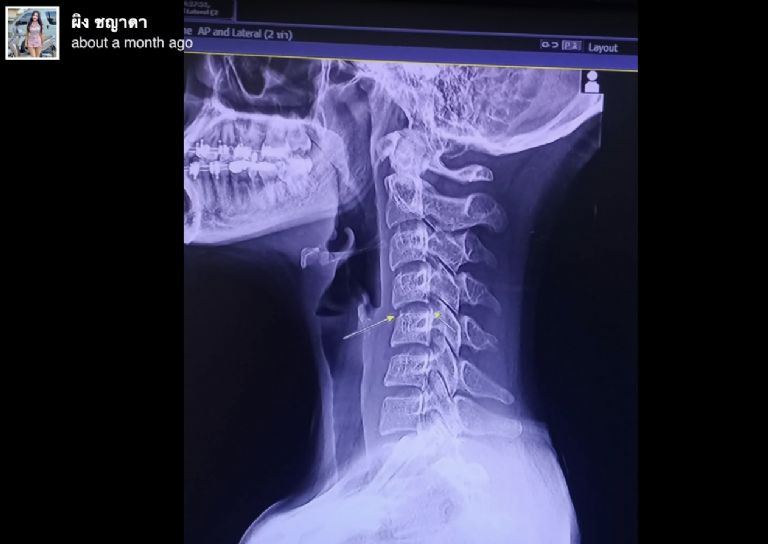

Según información de medios locales, la joven cantante se practicó unas radiografías cuando los duros malestares se hicieron inevitables. Estas evidenciaron la terrible realidad: que el hueso en su cuello se había movido sobre un nervio. Esto le provocó una parálisis que la dejó en cama y su cuerpo fue colapsando hasta tener que ser hospitalizada. La artista estuvo internada durante 10 días antes de morir.

Radiografía de la cantante